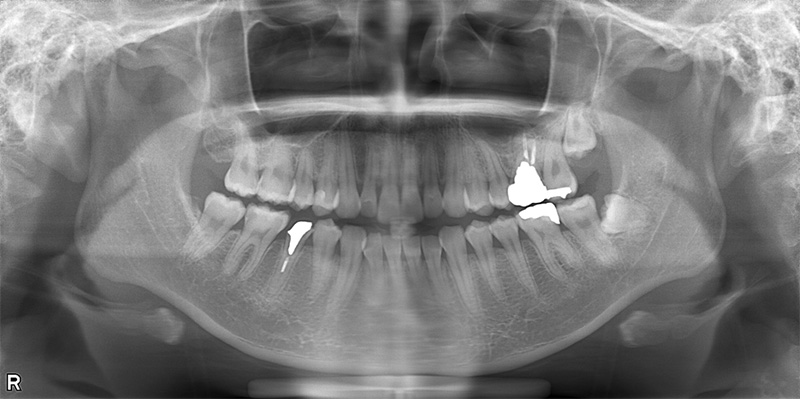

46歳女性

治療前

治療後

| 施術名 | インプラント治療 |

| 施術の説明 | インプラント治療とは、歯を抜いた所にチタン製の人工歯根を埋入し、新しく歯を入れる方法です。 |

| 施術の副作用 (リスク) | 腫れや疼痛を感じる、違和感を感じるなどの症状を生じることがあります。 |

| 施術の価格 | 53万円~+消費税 |